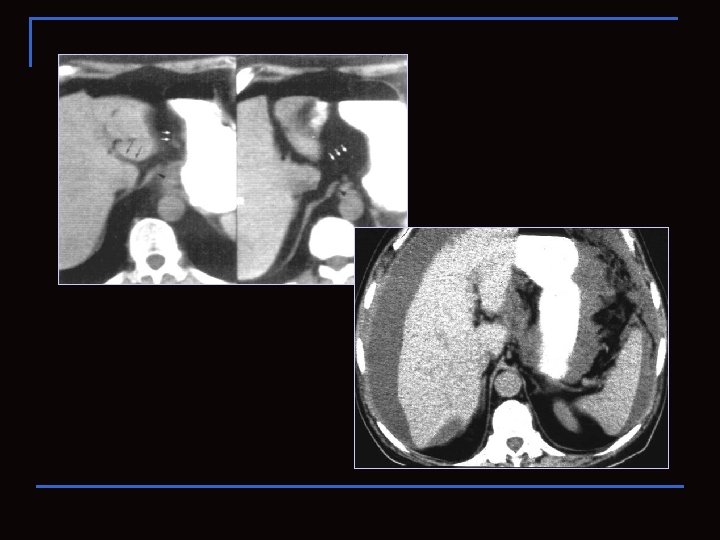

Subhepatický prostor Přední subhepatický prostor (ohraničený mesocolon transversum) Zadní subhepatický prostor = recessus hepatorenalis (Morrisonův prostor - v poloze na zádech nejnižší oddíl pravého supramezokolického prostoru). Subhepatický prostor je spojen se subfrenickým prostorem přes volný okraj jater. Morrisonův prostor Přední subhep. prostor

Hepatorenální prostor